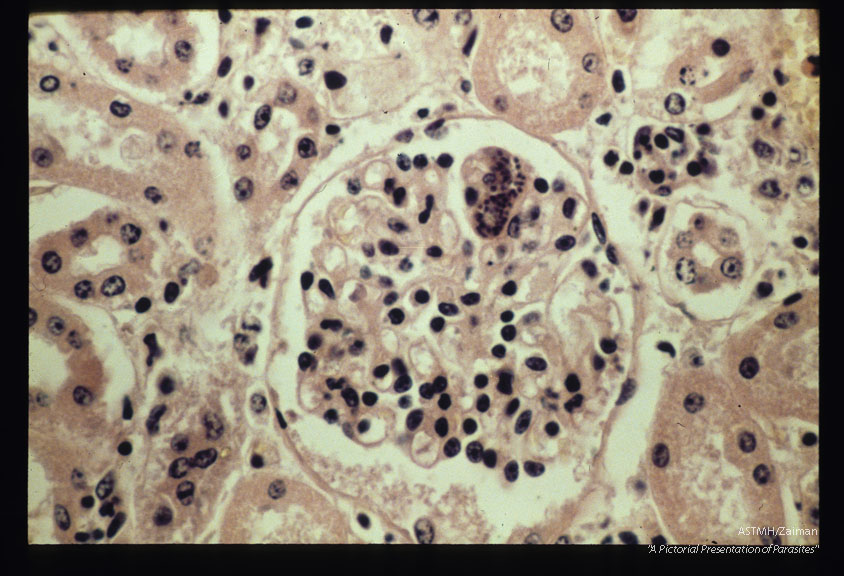

( = Sarcocystis cruzi, = Sarcocystis fusiformis). Schizont in endothelium of bovine kidney glomerulus.

Sarcocystis bovicanis

Description: ( = Sarcocystis cruzi, = Sarcocystis fusiformis). Schizont in endothelium of bovine kidney glomerulus.